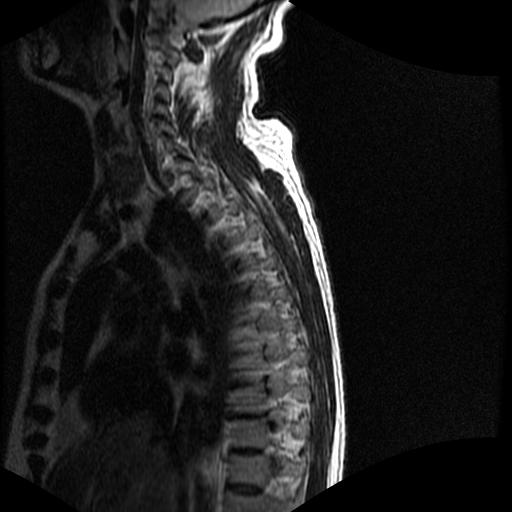

标题: MRI0985:胸椎.68岁男性,胸部疼痛,

68岁男性,胸部疼痛,不适。

t7椎体前1/3信号略减低,椎体上下面凹陷,相应脊髓几周边软组织信号未见改变。考虑:椎体退变。

胸7椎体楔状变形及信号异常,附件未见明显异常信号.椎间隙正常.未见软组织块影.考虑骨质疏松所致压缩性骨折可能大.

胸7椎体楔状变形及信号异常[t1t2 均为低信号],附件未见明显异常信号.椎间隙正常.未见软组织块影.考虑陈旧性压缩性骨折伴退变。

首先需除外单发成骨性转移瘤可能。

转移瘤也不能排除